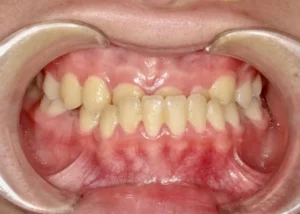

正面

- Before